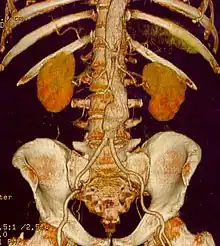

CT reconstruction image of an abdominal aortic aneurysm

A 6.5 cm AAA with a 3 cm lumen

An aortic aneurysm can occur as a result of trauma, infection, or, most commonly, from an intrinsic abnormality in the elastin and collagen components of the aortic wall. While definite genetic abnormalities were identified in true genetic syndromes (Marfan, Elher-Danlos and others) associated with aortic aneurysms, both thoracic and abdominal aortic aneurysms demonstrate a strong genetic component in their aetiology.[13]